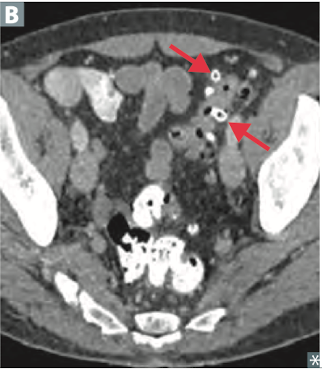

8

Q

What are the complications to diverticulitis?

A

Abscess, fistula, (colovesical fistula -> pneumaturia (stool and air in the urine), obstruction (inflammatory stenosis), perforation that can lead to peritonitis. Hematochezia is rare.

Treat with surgery and antibiotics.